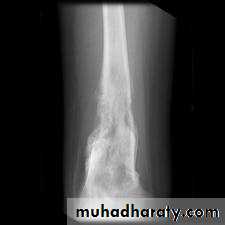

X-rays

variable hazy osteolytic .

areas may alternate with unusually dense Osteoblastic areas.The endosteal margin is poorly defined. often

The cortex is breached .

The tumour extends into the adjacent tissues; when this happens.

Streaks of new bone appear, radiating outwards from the cortex – the so-called ‘sunburst’ effect.Reactive new bone forms at the angles of periosteal elevation (Codman’s triangle).